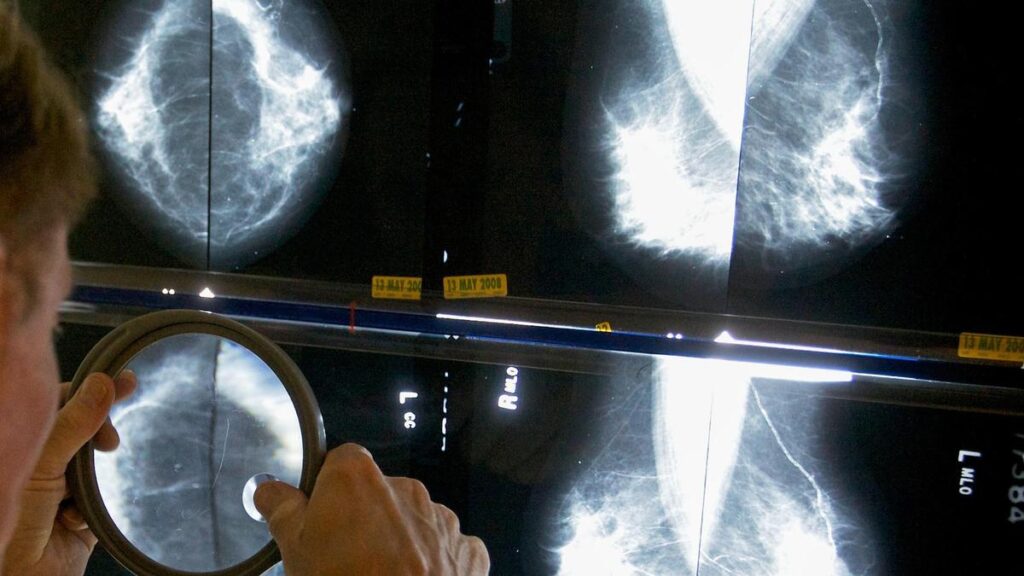

A radiologist uses a magnifying glass to check mammograms for breast cancer. File

| Photo Credit: AP